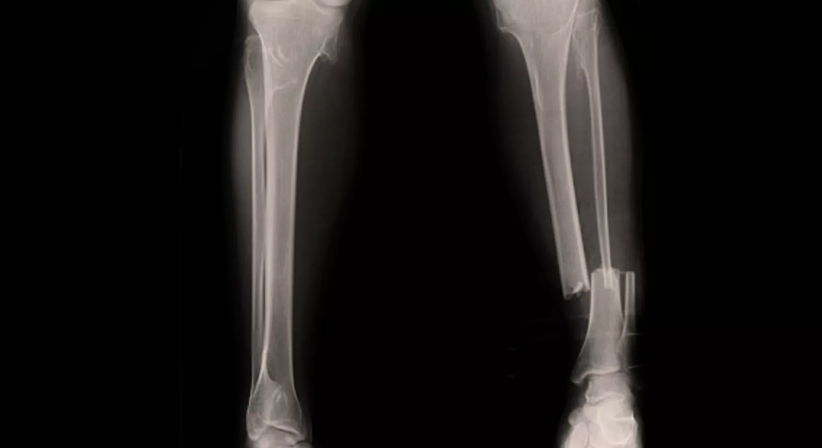

Der Unterschenkel besteht aus dem Schien- und Wadenbein (Tibia und Fibula). Kommt es zu einem Unterschenkelbruch, sind meist beide Knochen gebrochen. Natürlich kann die Fraktur auch nur einen der beiden Röhrenknochen betreffen. Als Marknagelung oder Marknagelosteosynthese wird das Operationsverfahren zur Behandlung von Röhrenknochenbrüchen bezeichnet.

Dabei wird ein sogenannter Marknagel (meist aus Edelstahl oder Titan) in den Markraum (Knochenmark) des Knochens eingebracht. Diese innere Schiene dient einer besseren Heilung und verursacht nur geringe Beschwerden. Das Tragen eines Gipsverbandes wird dem Patienten erspart. Nach ein bis zwei Jahren, je nach Heilungsverlauf, werden die Nägel wieder entfernt.